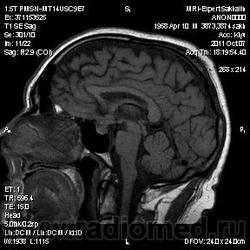

Аденома гипофиза

Вот такая аденома гипофиза сегодня.Мужчина с жалобами на снижение зрения.

постконтраст